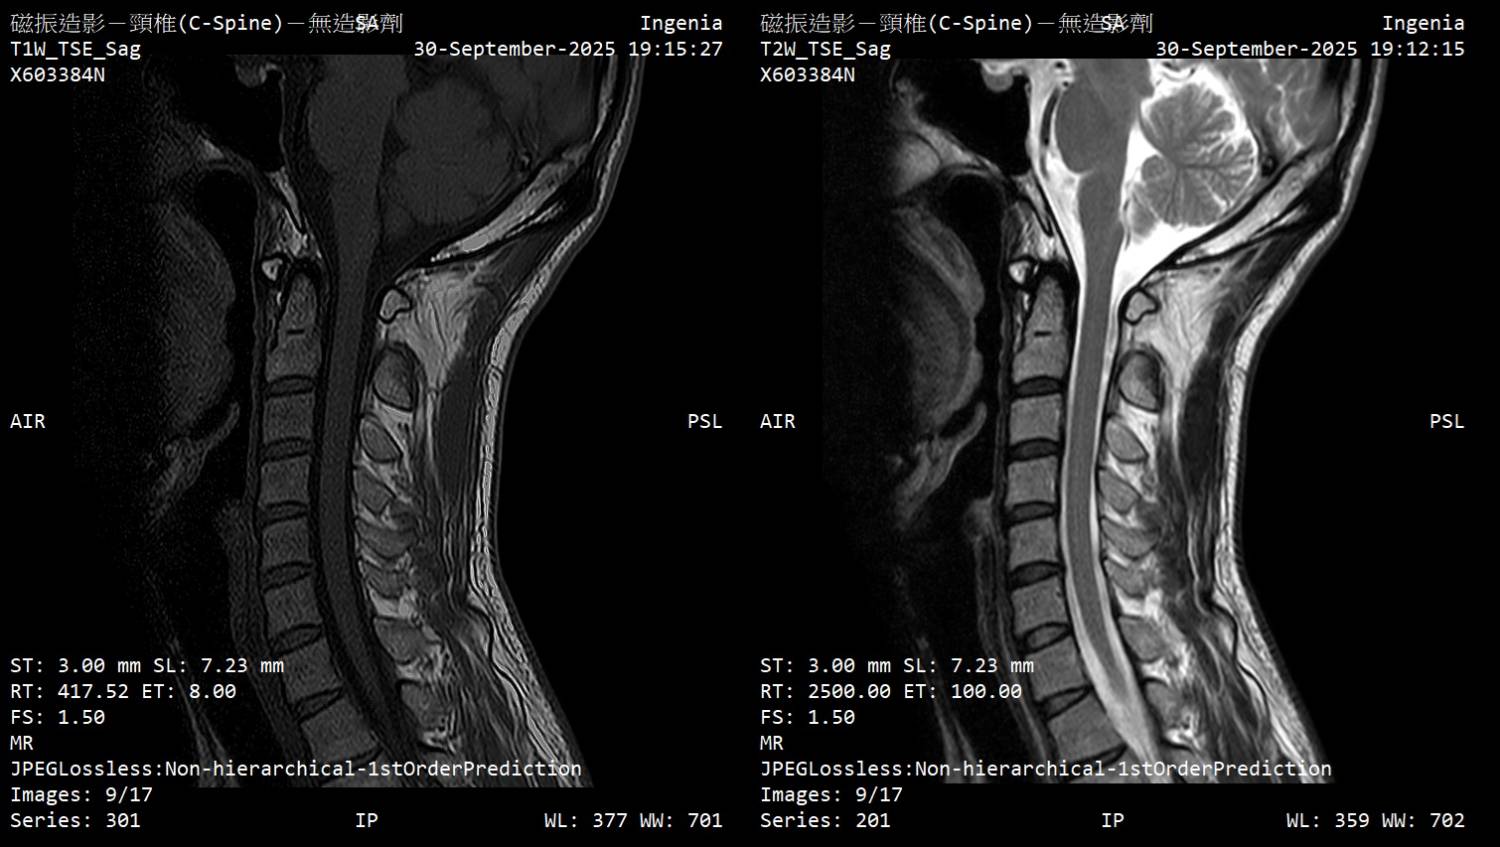

大家好 因为下列症状从2月开始断续发生,8月运动伸展上背後症状加剧 前往神经内科、神经外科就诊,目前不知道下步该往什麽方向? 该矫正姿势(脖前倾)? 复健科拉脖子? 寻求其他意见? 再观察? 症状 - 起床双手握不紧的感觉,白天正常 - 双手指尖感觉迟钝、左手臂外侧微麻感 - 双脚底有微微电流感(静止才感觉得到)、肌肉不定时抽动感、右小腿肚微麻 - 近半年有两次躺着以为有地震,结果没有震 检查 - 霍夫曼测试阳性、双膝反射增强 - 动作诱发电位正常、感觉诱发电位颈到手异常 11.3ms (标准<11ms) - 上肢神经传导正常 (一家正常/一家右正中神经异常) - 下肢神经传导左小腿/脚背异常 (以前受伤後遗症) 诊断 - 神内医师:颈椎有压迫、C5-C6黄韧带增生,建议先复健看看 - 神外医师:没有问题,应该是双手腕隧道症候群 颈椎MRI (全部) https://drive.google.com/drive/folders/1AmMB51gjrYYUIF8by9BEnTz1ahY3hbVp 文字报告 Unremarkable curvature of cervical spine No obvious herniated disc No obvious neuroforaman stenosis Suggest correlate clinical data. IMP: Unremarkable finding 神内医师判断可能压迫的部份 https://i.meee.com.tw/0E4JmY7.jpg

https://i.meee.com.tw/t3QgaWs.jpg

https://i.meee.com.tw/CsUmHf3.jpg

https://i.meee.com.tw/0C6bI5t.jpg